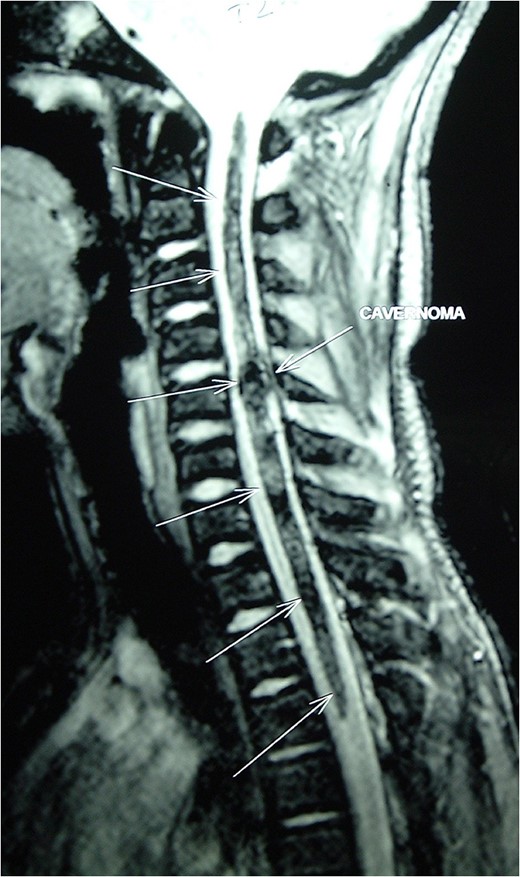

Magnetic resonance imaging (MRI) of the brain and spine showed multiple hypointense lesions in the brain and one mixed intense lesion with a hyperintense rim intrinsic to the spinal cord at the level of C5 with evidence of fresh bleeding (Figs 1–3). He was diagnosed with multiple cerebral cavernomas and an acutely bleeding spinal cavernoma. The patient was scheduled for a laminectomy and total excision of the spinal cavernoma and to control further hemorrhage. Bone removal was limited to the site of malformation. The lesion was identified by the bluish discoloration on the dorsal surface of the spinal cord (Fig. 4). A myelotomy was made over the discoloration and the lesion was excised inside out. Intraoperative evoked potential monitoring was not used for our procedure due to lack of availability.

MRI Brain (GRE T2WI) showing multiple hypointense lesions diagnosed as cerebral cavernomas.

Intramedullary spinal cavernomas may be associated with multiple concurrent occult cerebral cavernomas as seen in our case. This makes MRI of the complete neuraxis a crucial next step [1, 4, 5]. Familial CM syndrome should be suspected for any case with multiple cerebral cavernomas [4]. MRI remains the gold standard for diagnosing both cerebral and intramedullary cavernomas. They appear as mixed signal intensity lesions in on T1 and T2-weighted images surrounded by a low-signal intensity zone (due to hemosiderin deposits) best seen on T2-weighted images [4, 5, 8].